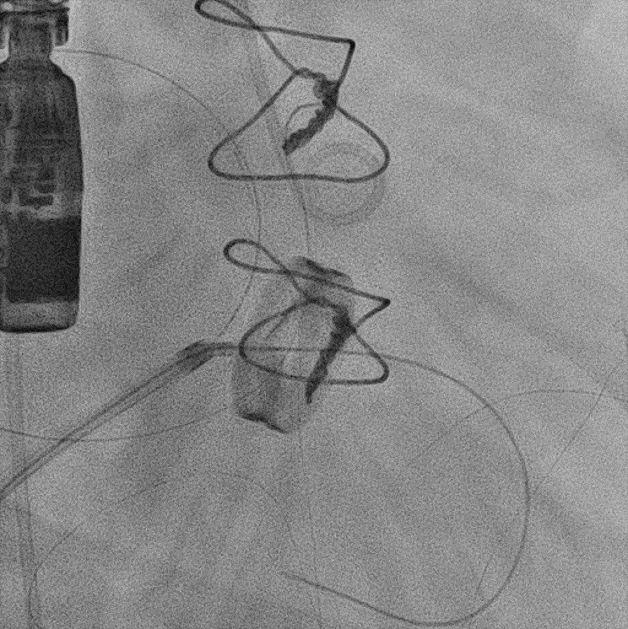

TEE, TEE and Floro showed both the leaflets to be stuck, almostno flow across the PV. The RV was higely dilated and there was severe RVdysfunction

Since TLT was not possible and surgeon refused for emergencyTranscatheter valve disruption was planned. The issues involve in the procedure were 1.Septal Puncture -due to pericardial patch in IAS, alteredanatomy due to Sx & ac dilatation of LA- Angle of puncture and Site ofpuncture. 2 Selection of wire3.Balloon- Size, make ( Compliant Vs NC), 4.Complication-like disc embolization, stuck disc leading to ac severe MA and strud fracture. The septa puncture was done as standard approach, a V18 wirewas parked in PV through a 7f Mullin sheath, Straight Turmo wire was was takenthrough a 6 JR to cross the valve and a 6 x 40 Armada balloon was dilatedacross the disc. Good acute result was obtained. The LA mean decreased from36-40 to 10-12mmHg. Post procedure the inotropic support, O2 demand decreasedover next 12 hr. However after 24 hr pt developed refractory RH failure and persistentanuria requiring SLED. And pt succumbed to the procedure 3 days after theprocedure.